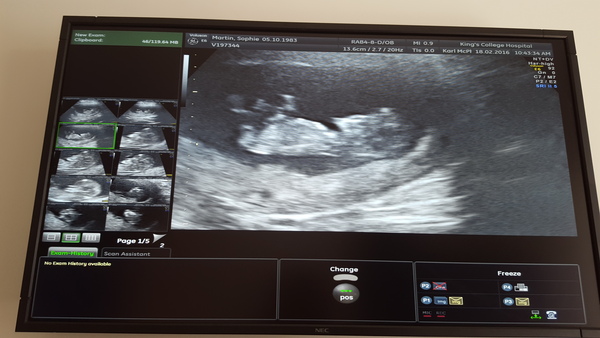

genome · 17/02/2016 18:15

I had my scan this afternoon and it shows one very wiggly baby! Hopefully the picture will have attached itself to this post.

Lovely cute baby there genome Smile

What a lovely clear scan, genome! Glad all is well. Just itching to get mine now and hope that all is ok.

My 20 week scan is the same day millie! I was suprised she got a good picture after chasing it around trying to get a nuchal measurement Grin The 12 week scan for my dd2 is really blurry as we had a similar chase the baby situation. Dd2 has never stopped moving since so I wonder if this baby will be the same!